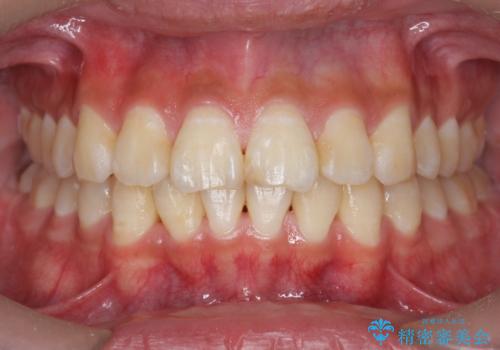

【モニター】処置歯の多い歯列 インビザラインでデコボコを整える